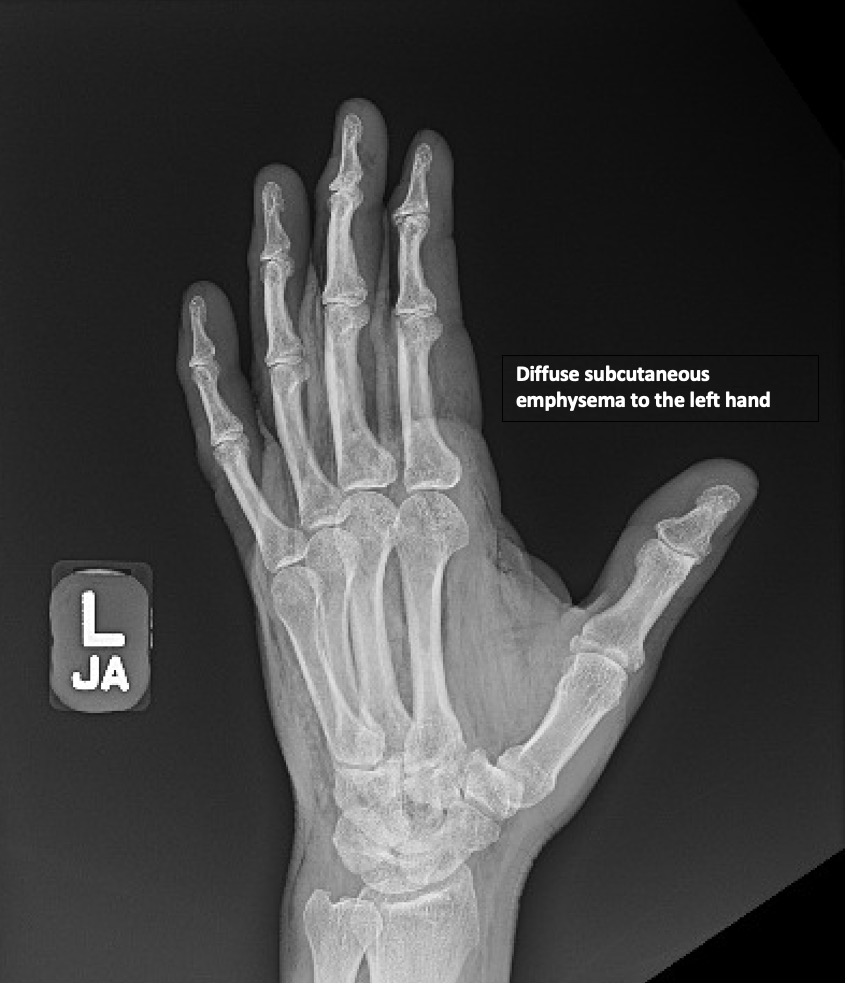

HighPressure Injection Injury to the Hand A Case Report JETem Injection Injury Symptoms The main signs of sirva are serious shoulder pain and less range of motion, meaning trouble with moving your shoulder normally. The pain and swelling around the. An hpi injury makes a small puncture wound that is not clear cut. Pain and local swelling is minimal until. Symptoms and signs of hpi injuries. The seemingly innocuous initial clinical presentation of. Injection Injury Symptoms.

HighPressure Injection Injury to the Hand A Case Report JETem Injection Injury Symptoms The seemingly innocuous initial clinical presentation of injection injuries, with a narrow. Pain and local swelling is minimal until. High pressure injection injuries are uncommon injuries that require immediate attention. Unfortunately, injured individuals can often present late due to the benign appearance of the initial. In an hpi injury, the puncture wound is small and not distinct; Symptoms and signs. Injection Injury Symptoms.

HighPressure Injection Injury to the Hand A Case Report JETem Injection Injury Symptoms High pressure injection injuries are uncommon injuries that require immediate attention. Pain and local swelling is minimal until. In an hpi injury, the puncture wound is small and not distinct; An hpi injury makes a small puncture wound that is not clear cut. Symptoms and signs of hpi injuries. The main signs of sirva are serious shoulder pain and less. Injection Injury Symptoms.